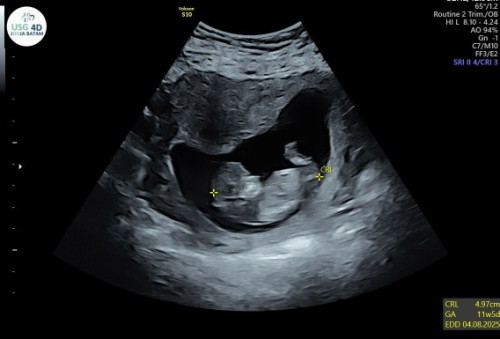

Bunda² adakah yg HPL bulan ini? UK 38w3d tpi dedek masih anteng² aja, tmen barengannya udh pda lahir.. Kalo bunda² udh merasakan apa aja di UK sgtu? Minta doa nya jga ya bunda² smoga kelahiran debay di beri kelancaran,sehat keduanya tanpa kurang suatu apapun 😇🙏🏻 #seriusnanya #bantusharing #pleasehelp #firstbaby #BantuJawabBundaCantik #ingintahu